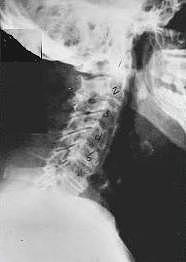

Near Normal

This is a side x-ray view of the neck.  As with all the pictures you will see on this page, the patient is looking to the right of the screen, so you are viewing the right side of their neck.  We will call this picture a "near normal" spine.  Compare this spine with the ones you will see below on this page.  Notice the normal forward curve of the neck.  This curve helps absorb shock.  Notice how each of the disc spaces between C2 (second bone in neck) and C7 are thick and even, this again is normal.  Also notice how the front portions (right on the x-ray) of each of the vertebrae (called the 'body' of the vertebrae) are fairly square with clear and well defined borders. This type of arrangement is normal in the neck.  Normal vertebrae in other parts of the spine also have similar characteristics to what we see here. When subluxations occur and are left uncorrected, ongoing relentless changes occur that result in damage to the structure and function of the spine along with nerve damage and the resulting problems caused from improper nerve supply.